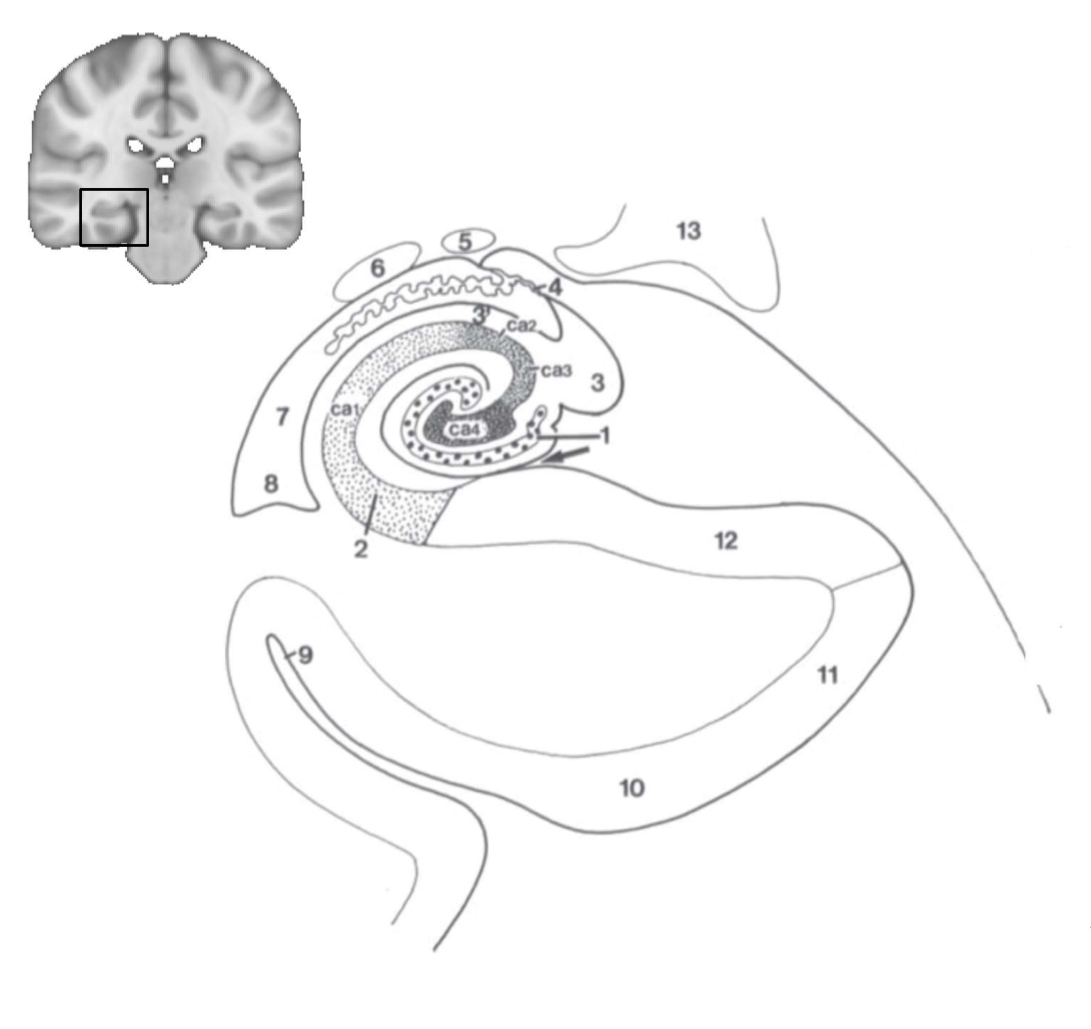

What structure is this?

hippocampus

What is 1?

hippocampus

What is 2?

rhinal sulcus

What is 3?

lateral ventricle

What is 4?

thalamus

What is 5?

entorhinal cortex

What is 6?

perirhinal cortex

What is 7?

parahippocampal cortex

What is 1?

gyrus dentatus

What is 2?

cornu ammonis

What is 3?

fimbria

What is 3’?

alveus

What is the arrow pointing to?

happicampal sulcus

What is ca1, ca2, ca3 and ca4?

fields of cornu ammonis

What is 4?

tela choroidea

What is 5?

stria terminalis

What is 6?

tail of caudate nucleus

What is 7?

temporal horn of lateral ventricle

What is 8?

collateral eminence

What is 9?

collateral sulcus

What is 10?

parahippocampal

What is 11?

entorhinal area

What is 12?

subiculum

What is 13?

lateral geniculate body